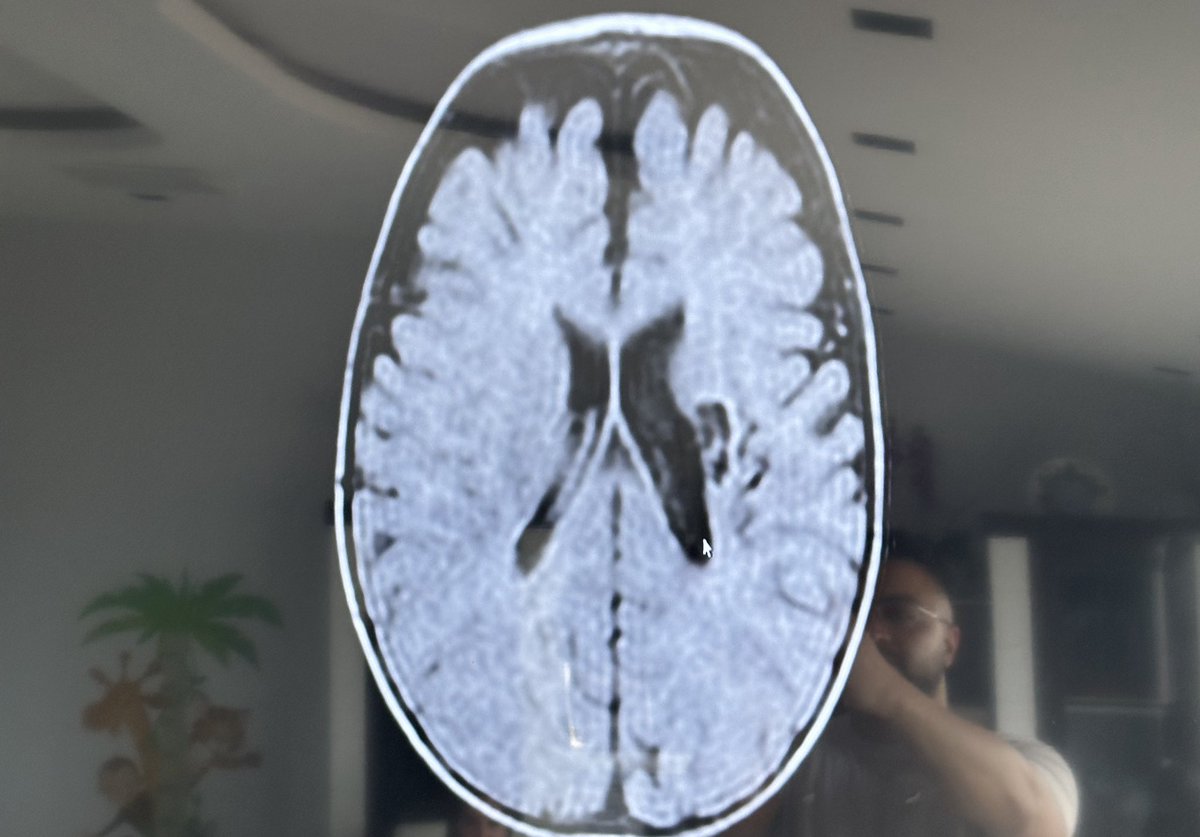

Right now my entire focus is away from crypto because my newborn son had a brain infarction at birth due to lack of oxygen. At the hospital we were told everything was fine. Weeks later something in me felt wrong and I insisted on an MRI.

The MRI confirmed brain damage. He has cerebral palsy on the left side of his brain which affects the right side of his body. As a parent this news breaks you in ways that are hard to describe.